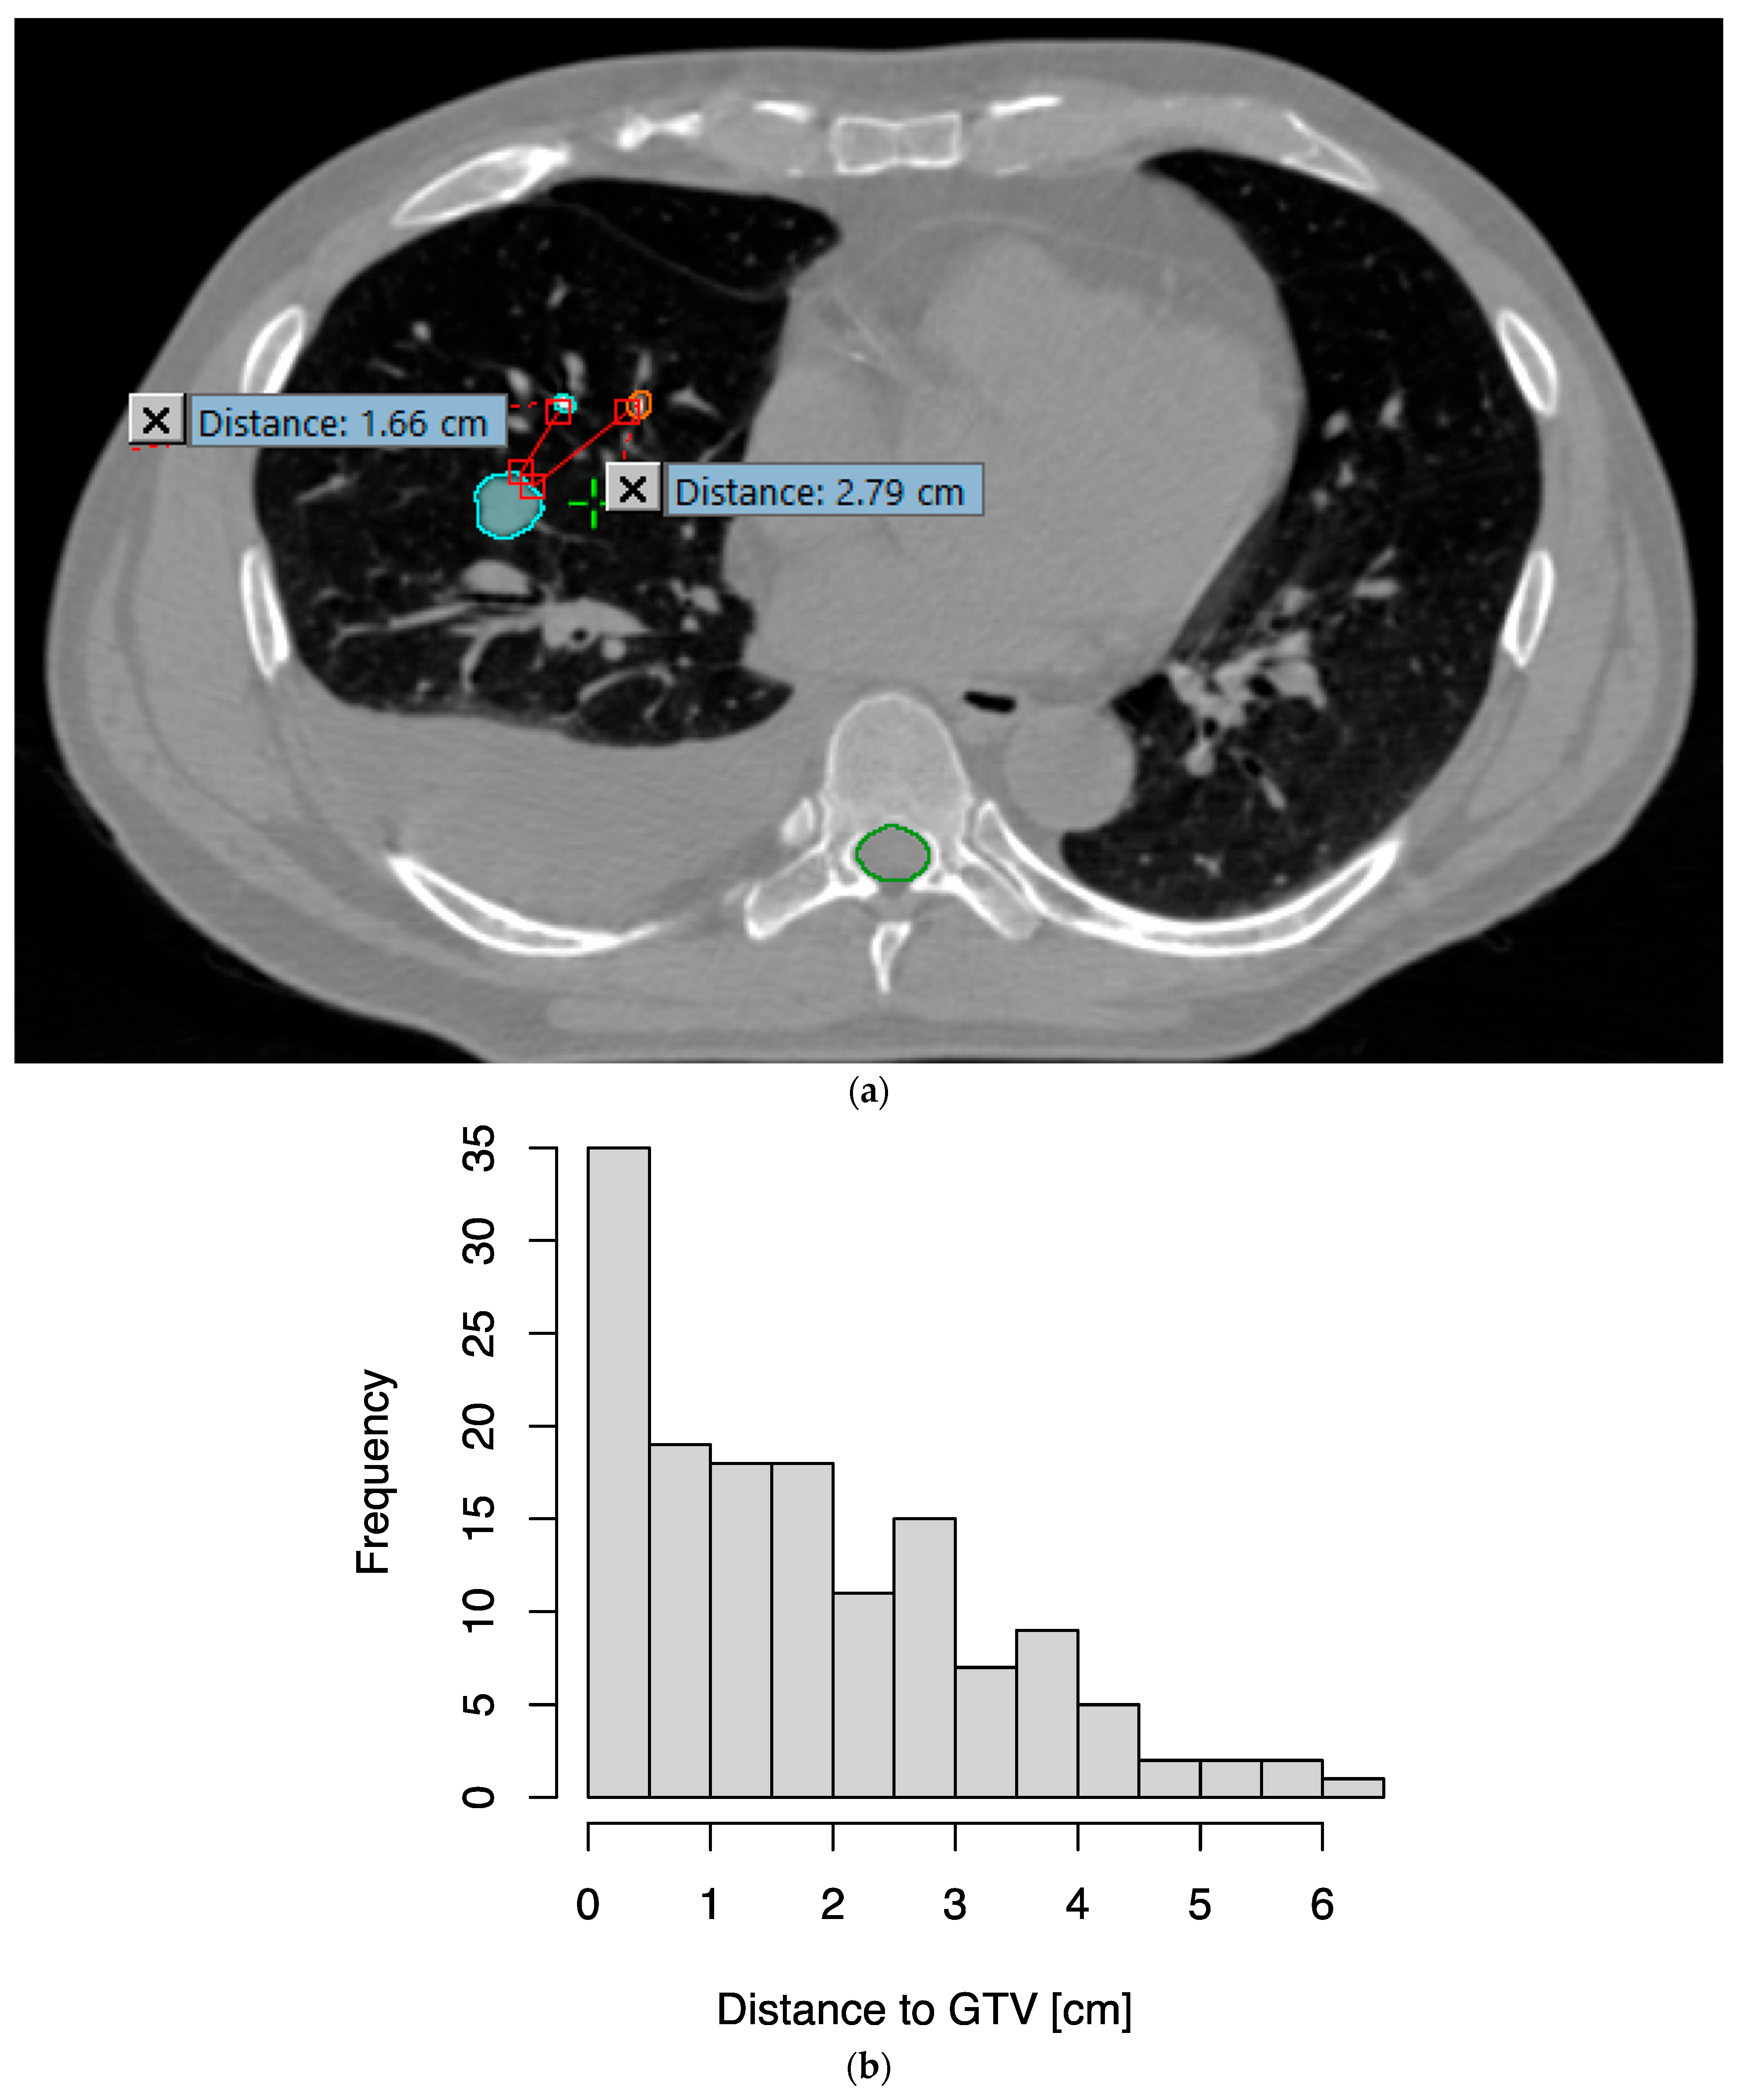

3.2. EMTs Were Implanted Close to the Tumor with Low Toxicity